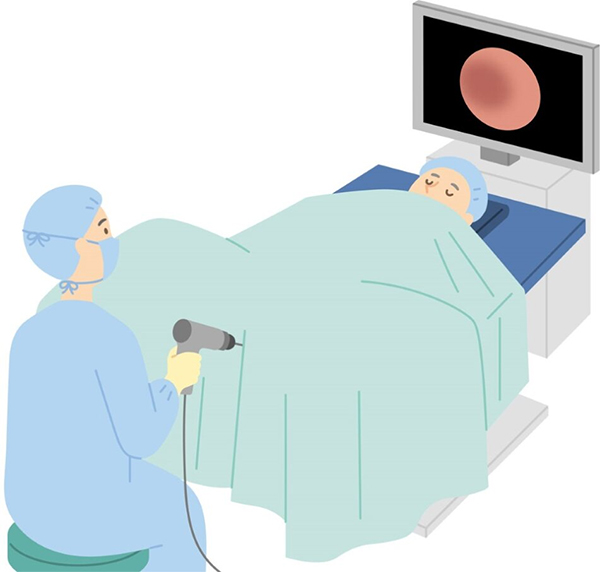

Rezumシステムは、内視鏡を用いて尿道から入り、水蒸気を利用して前立腺肥大症を治療する医療機器です。

①手術前(手術別日)に尿道膀胱鏡検査を行い前立腺の状況を確認します。

- 前立腺肥大症の程度を確認することはもちろんですが、排尿障害の原因として、前立腺肥大症とは別の疾患の有無(尿道狭窄症や、尿路結石症などのの有無)が無いかを確認するためです。

- 仙骨硬膜外麻酔+尿道粘膜麻酔(場合によっては静脈麻酔)を行います。

- 麻酔施行15分後より砕石位(お産の体位)にて手術を行います。

- 約10〜20分で手術は終了します。